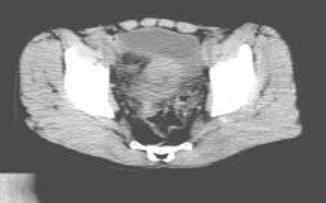

病历摘要:男,54岁病史:间歇性肉眼血尿伴下腹部隐痛7月余。为全程血尿,浓茶色,并有尿频尿急尿痛。当地医院曾造影检查示“膀胱结石”,入院前3天当地医院检查示“膀胱肿瘤”体查:心肺腹无明显阳性体征,双肾区无叩痛,双输尿管行程无压痛点,膀胱区未见肿胀、隆起实验室检查:尿常规:淡黄色,混浊,潜血大量,镜检白细胞370/μl(↑)